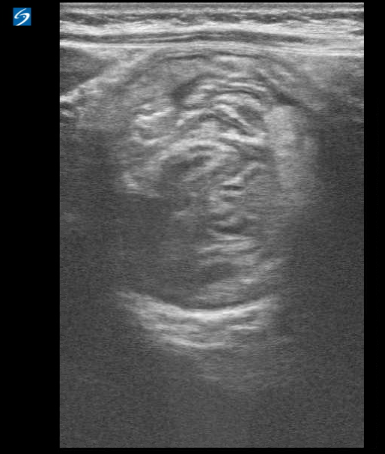

Intussisception appears as a non-compressible, target-shaped mass with concentric echogenic and hypoechoic rings on the transverse view and as a “pseudokidney” or “stack of pancakes” on the longitudinal views (Fig. 4 and Fig. 5 a,b,c).1,3,4 The important characteristic appearance on transverse scan is the presence of the central/eccentric and hyperechoic mesenteric fat, that is pulled with vessels and lymph nodes into the intussusception by the intussusceptum; which differentiates from other entities, such as bowel hematoma, stool, bowel wall edema, mass, or even a psoas muscle.9 Doppler ultrasonography can also be useful to detect and evaluate blood flow. The absence of flow is a sign that surgical reduction may be necessary.4

(Figure 6a: Left) (Figure 6b: Center) (Figure 6c: Right)

Figure 6a-6c. Right lower quadrant ultrasound, transverse (a) and longitudinal views (b). (c) Layered 3.4 cm appearance mass is identified in the right lower quadrant, interposed hypo/hyper echogenic layers, with central hyperechoic mesentery fat, representing the intussusceptum (arrow).